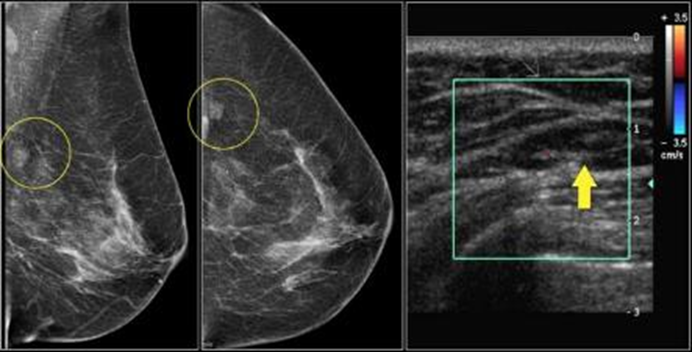

Mammography is an imaging modality that uses low energy x-rays specifically for imaging of breast tissue. Each breast is examined separately and compressed against the film to obtain maximum visualization of masses or calcification. Numerous studies show that breast cancer is the most common cancer to affect women, however with early screening and quality treatment the survival rate significantly increases, as it plays a central role in the early detection of breast cancer and other breast diseases

Breast tomosynthesis, also called three-dimensional (3-D) mammography and digital breast tomosynthesis (DBT), is an advanced form of breast imaging, or mammography, that uses a low-dose x-ray system and computer reconstructions to create three-dimensional images of the breasts. It reduces the rate of false positive readings (a reading that identifies normal tissue as an abnormality) and ensures that fewer women need to come back for another mammogram. It reduces the need for a biopsy and enables the healthcare provider to more accurately locate where the abnormality is in the breast.

Stereotactic and Vacuum Biopsy

Accurate computer imagaing guidance allows precise localization of breast lesions which can be sampled by biopsy or removed with vacuum assisted biopsy. Vacuum assisted biopsy is an alternative to surgical biopsy and is performed under local anaesthetic.